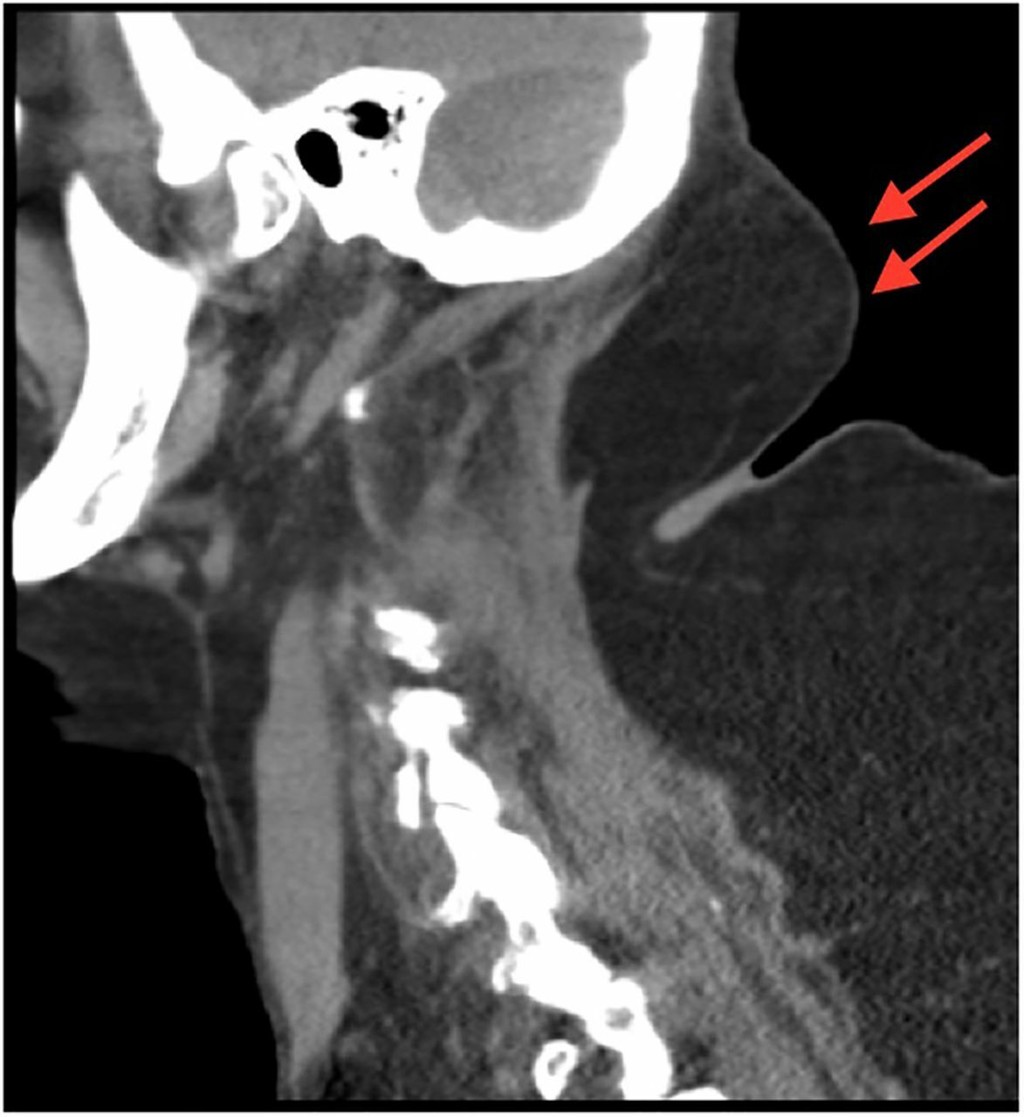

Hrby boli nádory, najväčší mala na chrbte. Lekári si pomáhali ešte aj internetom, robili jej testy, až nakoniec prišli na to, že žena trpí Madelungovou chorobou. A príčina bola alkohol. Práve alkoholici ňou trpia najviac. Celú vrchnú časť tela má pokrytú lipómami.

„Na prvý pohľad sme zaznamenali množstvo opuchov po celom tele, najmä na krku, vrchnej časti chrbta a horných končatinách," povedali pre BMJ Case reports lekári. Krvné testy ukázali prítomnosť ketónov, ktorý sa nachádza väčšinou u ľudí s cukrovkou. Žena však má nádej na uzdravenie. Nesmie piť a musí ísť na liposukciu.